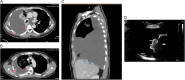

Figure 1

(A) Massive pleural effusion, shifting mediastinum to contralateral. (B) Reduced pleural effusion after inserting chest tube.